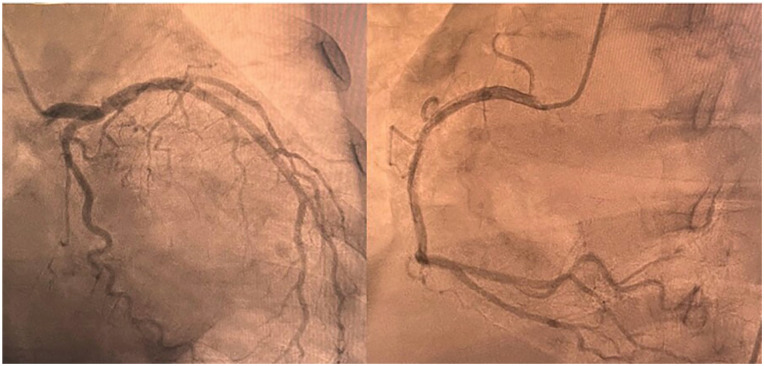

Wellens' syndrome is characterized by a distinct electrocardiographic pattern, most notably biphasic or deeply inverted T waves in the anterior precordial leads, particularly V2 and V3. These findings typically reflect transient myocardial ischemia resulting from critical stenosis of the proximal left anterior descending (LAD) artery. They are often a warning sign of an impending anterior wall myocardial infarction. However, conditions such as pseudo-Wellens' syndrome can exhibit similar electrocardiogram (ECG) changes without LAD occlusion. In this case report, we describe a 71-year-old woman who presented with chest discomfort and dyspnea and was ultimately diagnosed with sepsis-induced cardiomyopathy, which produced ECG changes mimicking Wellens' syndrome despite the absence of coronary artery disease; cardiac catheterization found no significant coronary pathology. The diagnosis was determined to be stress-induced cardiomyopathy resulting from sepsis. This report highlights the importance of distinguishing between ischemic and nonischemic causes of similar ECG patterns. It emphasizes the necessity for careful diagnosis and management, particularly in complex situations like sepsis.